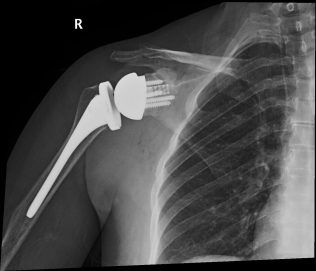

أجرى الدكتور فيد بي جوسوامي الجراحة في الخامس من مايو 2023 في ميديكلينيك مستشفى المدينة، دبي ، الإمارات العربية المتحدة، على الكتف الأيمن للسيدة إي، وهي من سكان دبي، والتي تسبب التهاب المفاصل الحاد فيها بألم شديد في مفاصلها. كان كتفها شديد الصلابة مع خسارة كبيرة في العظام ومع عدم انتظام مقبض الكتف. حيث قدم نظام الجراحة بمساعدة الحاسوب ExactechGPS نموذجاً ثلاثي الأبعاد في الوقت الفعلي لكتف المريضة، مما مكن د. جوسوامي من إعادة بناء المقبس باستخدام غرسة معززة لاستعادة المحاذاة أثناء إجراء الاستبدال العكسي.